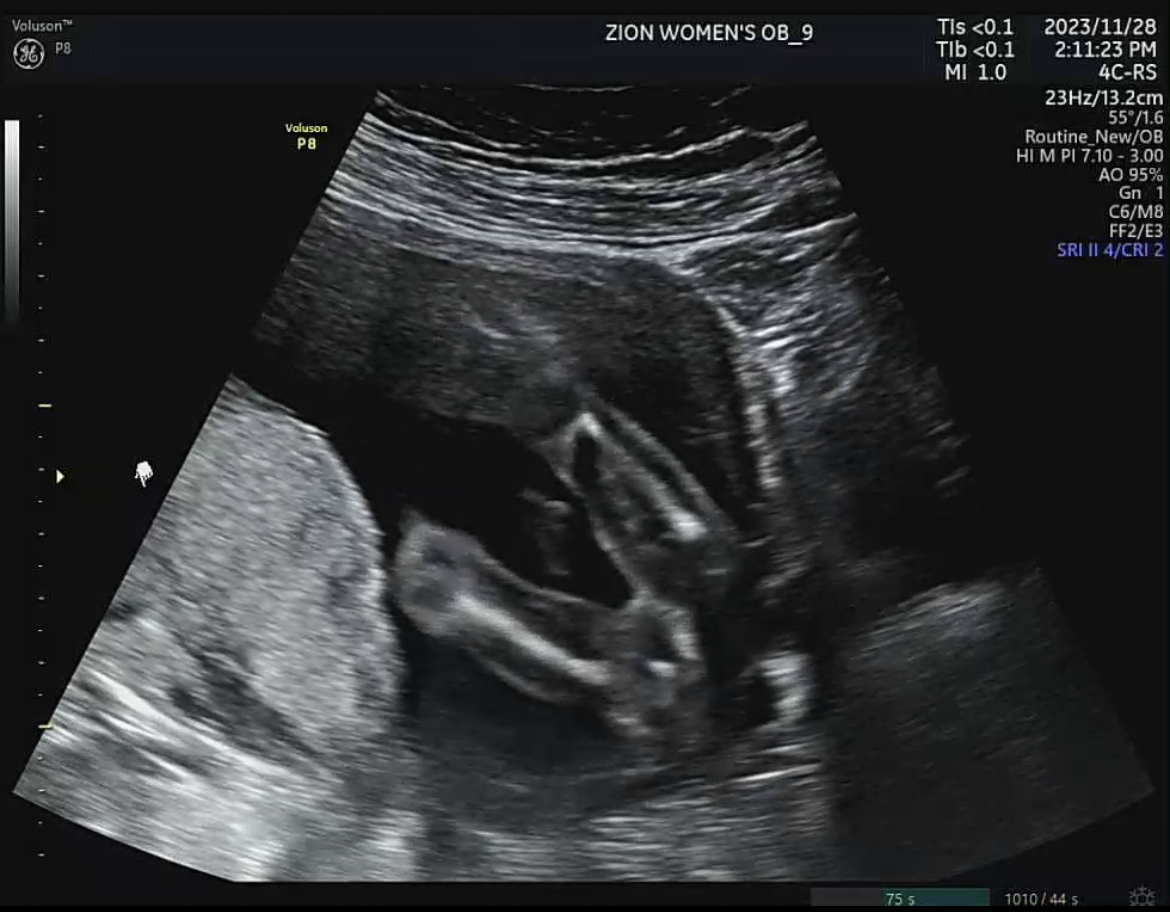

4. 12주 각도법(장꾸맘의 각도법) 성별 확인 방법: 12주 이후 (딸 = 맞춤)

가. 12주 각도법

태아 초음파에서 옆모습의 척추와 성기의 각도를 통해 볼 수 있는 방법을 12주 각도법이라고 부릅니다. 12주보다 좀 더 이르면 애매할 수도 있고, 12주가 지나면 성기의 형태로도 추정할 수 있기 때문에 가장 빠르게 성별을 확인할 수 있는 방법입니다. 툭 튀어나온 부위가 척추와 평행을 이루고 있다면 딸, 30도정도의 각도를 이루고 있다면 아들이라고 합니다. 16주 이상 됬을 때 정확한 성별을 판단하기 이전에 가장 정확하게 확인 할 수 있는 방법입니다.

장꾸맘님의 주변 적중률은 100%였고, 인터넷상으로 돌아다니는 적중률도 99%는 되는듯합니다. 일단, 확실할 경우에는 딸에 한표요! 아들에 한표요! 라고 말씀해 주시고, 정말 안보이시는 동영상의 경우 업로드 재요청을 해주시거나, 조건부로 잘 보이지 않는 동영상이지만, 혹은 조심스럽게, ~에 한표요 라고 얘기해 주신답니다. 저의 경우에는 12주2일차 동영상을 올렸고 단답으로 딸에 한표요! 라고 답변해 주셨답니다.

처음말씀드린 바와 같이 16주~20주가 되면 아이의 성별은 병원에서도 확인 가능합니다.(일부 병원은 성별에 대한 언급은 안 해준다고 합니다.) 제가 테스트했던 4가지 방법 중 난황을 제외하고는 딸로 모두 적중했습니다. 16주가 되었을 때 아래 사진과 같이 남아와 여아의 성기가 변화되기 때문에 엉덩이 사진만으로도 성별 확인이 가능하답니다.